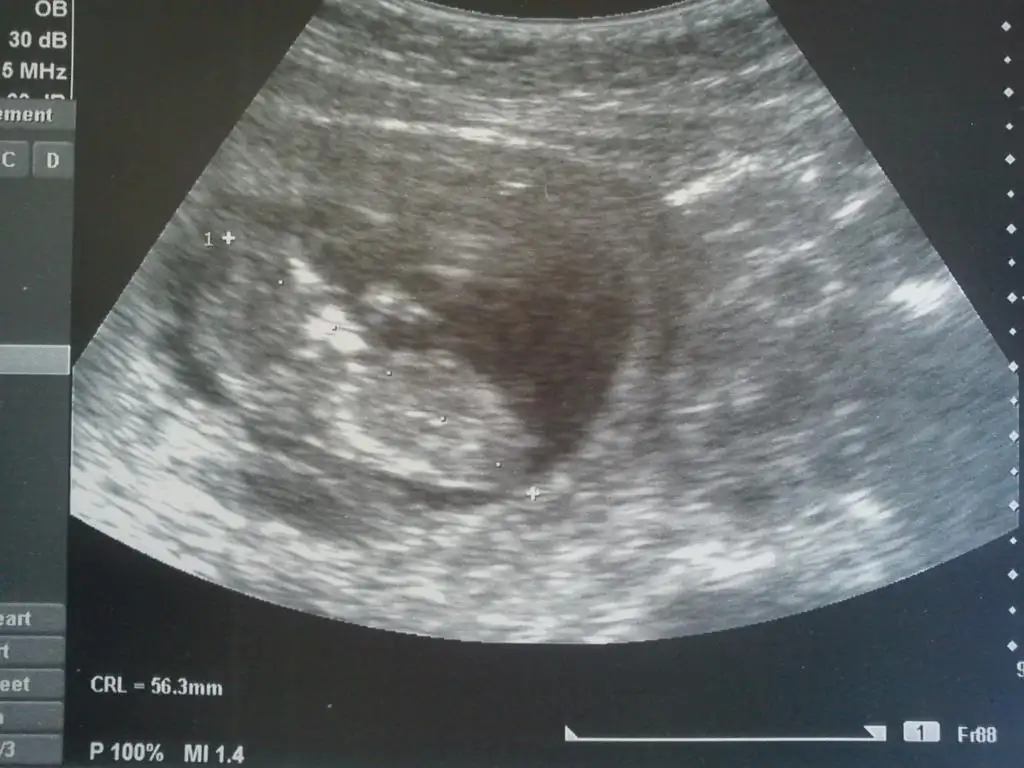

Merhaba arkadaşlar benimde bebeğime bakarmısınız:) dün çekildi 12+5 dedi doktor ama cinsiyetini söylemedi kesin olsun öyle söylerim dedi. Cinsiyeti benim için hiç önemli değil ilk olacak kuzum benim ama merak işte :) Çıkıntısına göre bana kız gibi geldi bebişim birde size sormak istedim

Nub paralel gibi,benim fikrim kız.